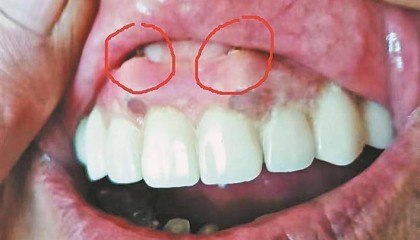

绥化刘先生反映其母亲种牙后,牙龈鼓俩大包,顶嘴唇!哈尔滨市优诺口腔回应

15日,绥化市刘先生通过生活报热线反映,其母亲姜大娘在哈市道里区群力第五大道518号金鼎文化广场一...